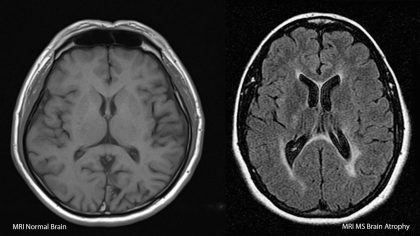

Kesehatan | • September 28, 2025 • Multiple Sclerosis: Definisi, Penyebab, Gejala dan Pengobatan Penyakit saraf yang dikenal sebagai multiple sclerosis (MS) telah menjadi perhatian global dalam beberapa tahun...